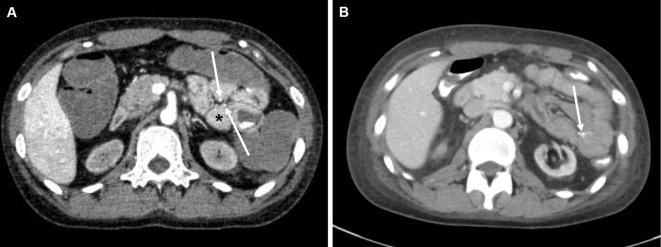

A 21-year-old woman was admitted to our hospital because of massive intestinal bleeding. She started hemodialysis due to myeloperoxidase antineutrophil cytoplasmic antibody (ANCA)-associated vasculitis (AAV) at 18 years of age. Her ANCA titers remained stable; however, her C-reactive protein increased on 5 mg/day prednisolone before admission. Computed tomography angiography revealed a ruptured jejunal arterial aneurysm. Transcatheter arterial embolization, blood transfusion and the reinforcement of steroid therapy resolved her symptoms of AAV. Our case of a young patient with AAV and medium-sized arterial vasculitis is rare and emphasizes that the ANCA titer does not always rise, especially in patients with nonrenal vasculitis flare-ups.

一位 21 岁女性因大量肠道出血而入院。她在 18 岁时因髓过氧化物酶抗中性粒细胞胞质抗体(ANCA)相关性血管炎(AAV)开始接受血液透析。她的 ANCA 滴度保持稳定;然而,在入院前,她每天服用 5 毫克泼尼松龙,C 反应蛋白升高。计算机断层血管造影显示空肠动脉破裂性动脉瘤。经导管动脉栓塞、输血和强化激素治疗缓解了她的 AAV 症状。我们的这个年轻 AAV 合并中等大小动脉血管炎的病例比较少见,强调了 ANCA 滴度并不总是升高,尤其是在非肾血管炎发作的患者中。